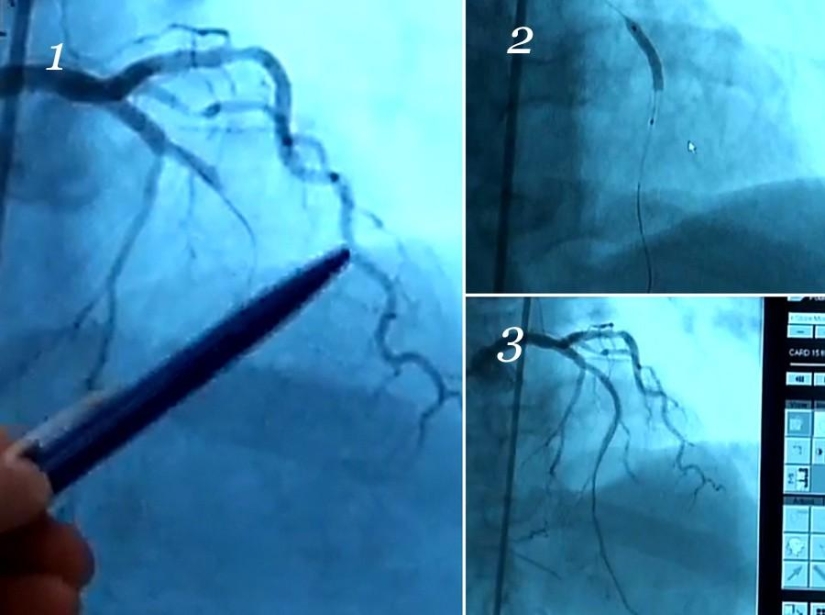

15. And here is how the stent works. These are screenshots from the X-ray TV.

In the first picture, we see only one artery, a curly one. But another one should be visible, below it. Because of the plaque, the blood flow is completely blocked.

The thick sausage on the second is a stent that has just been deployed. The arteries are not visible because the contrast is not running in them, but the wires are just visible.

The third one shows the result. An artery appeared, blood flowed. Now compare the first picture with the third one again.